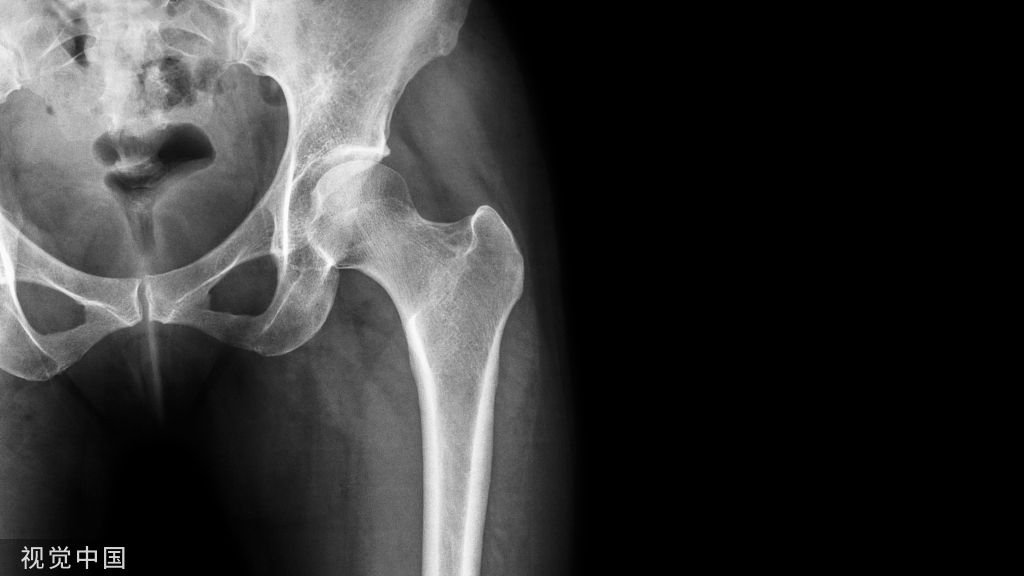

干骺端长斜形骨折采用髓内钉固定的难点之一为骨折对线的恢复,由于骨折暴力因素或骨折周围肌肉的牵拉,断端间通常存在侧方移位趋势,在髓内钉置入时如何纠正骨折断端对位对线是临床较常见问题。

图1 股骨远端骨折示例。沿股骨远端骨块作一中轴线,骨折线与中轴线相交,形成2锐角(Acute angles)。